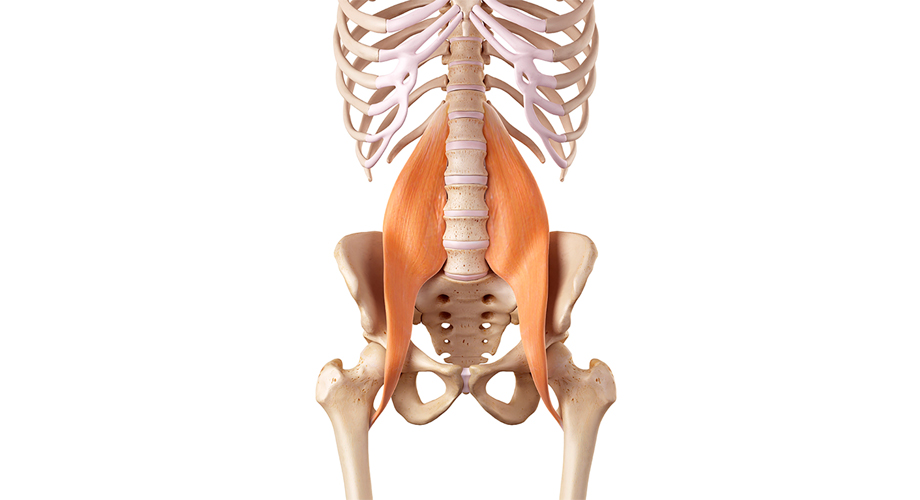

허리디스크란 척추뼈 사이에 있는 디스크가 손상되어 신경을 압박하는 질환을 의미합니다. 디스크는 척추뼈 사이의 충격을 흡수하고 척추의 움직임을 부드럽게 해주는 역할을 하는데, 이 디스크가 손상되면 신경을 압박하여 통증, 마비, 감각 이상 등의 증상이 나타납니다.

또한 나이가 들면서 디스크의 수분 함량이 감소하고 섬유륜(※섬유륜 이란? 척추 사이 원반의 바깥 부분을 고리처럼 이루는 섬유 연골과 섬유 조직을 의. 이것이 약해졌을 때 속질핵이 빠져나가 척추 원반 탈출증을 일으킬 수 있다.)이 약해지면서 허리디스크가 발생할 수 있습니다.